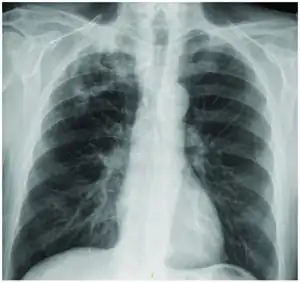

Mycobacterium interjectum lung infection

According to the medical literature Mycobacterium interjectum can cause the following:[1]

- Lung infection